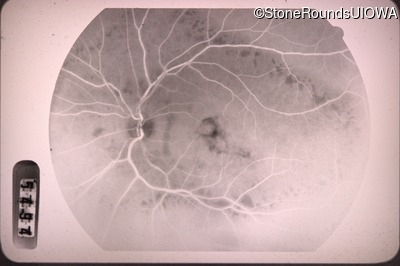

Fluorescein Angiography - Left - 20/40 -1

Exemplar